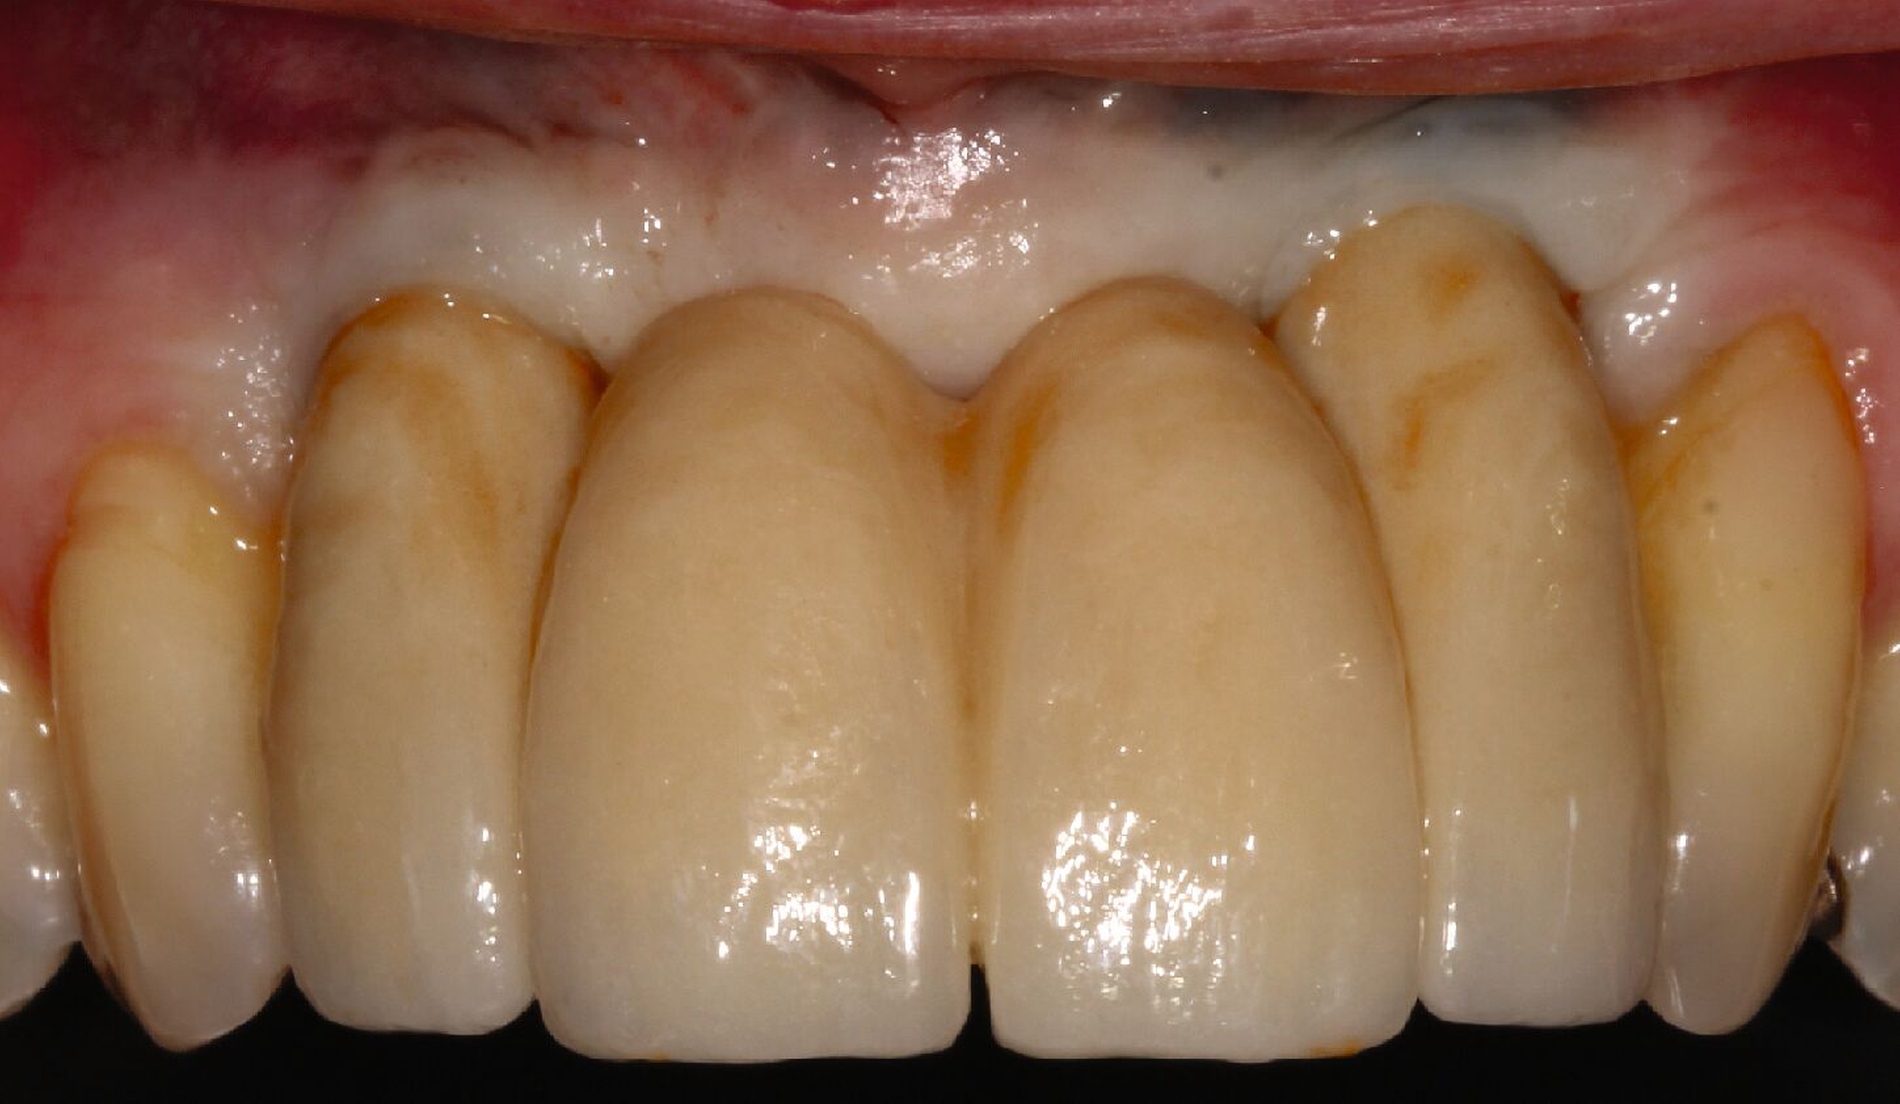

Ursprünglich waren bei dieser Patientin nach einem Frontzahntrauma vier Implantat-gestützte Kronen geplant. Nach dem frühen Verlust des Implantats in regio 21 während der Einheilzeit wurde dann eine auf drei Implantaten abgestützte Brücke eingegliedert. Das bestehende vertikale und horizontale Weichgewebsdefizit wurde bei der verschraubten Implantatbrücke durch aufgebrannte rosafarbene Keramik kaschiert (Abb. 3a). Funktionell war die Brückenversorgung über viele Jahre erfolgreich und zeigte keinerlei Lockerungsgrad. Trotz guter Mundhygiene war in Kontrollsitzungen ein kontinuierlicher Knochenabbau an allen Implantaten festzustellen (Abb. 3b). Zur Vermeidung eines weiteren Knochenverlusts fiel circa 15 Jahre nach der Erstversorgung die Entscheidung zur Explantation. Zu diesem Zeitpunkt war die Patientin 55 Jahre alt.

Nach dem Abschrauben der Suprastruktur (Abb. 3c und 3d) wurden alle Implantate unter Lokalanästhesie mit einem passenden Trepanbohrer umbohrt und ohne Lappenbildung entfernt. Die temporäre Lückenversorgung erfolgte mit einer herausnehmbaren Prothese, die über Gussklammern am Restgebiss abgestützt war.

Da sechs Monate nach der Explantation keine nennenswerte knöcherne Regeneration festzustellen war, wurde eine zweizeitige Implantation nach Knochenaugmentation mithilfe dünner Knochenscheiben aus dem Kieferwinkel geplant. Die Entnahme erfolgte mit oszillierenden Instrumenten (Piezosurgery). Der Knochenblock wurde in dünne Scheiben geschnitten und mit Osteosyntheseschrauben am Alveolarfortsatz fixiert (Abb. 3e). Darüber wurden die Weichgewebe dicht vernäht. Weitere fünf Monate später erfolgte die Schraubenentfernung und die Implantation von zwei Bone-Level-Implantaten in regio 12 und 22 mit geschlossener Einheilung (Abb. 3f und 3g). Bei der Implantatfreilegung weitere sechs Monate später wurden die Weichgewebsdefizite im Brückengliedbereich durch ein kombiniertes Bindegewebs-/Schleimhauttransplantat aufgefüllt und gleichzeitig die keratinisierte periimplantäre Gingiva und Alveloarmukosa verbreitert (Abb. 3h und 3i). Die prothetische Versorgung erfolgte erst weitere drei Monate später, nach dem Konsolidieren der Weichgewebe. Die umfangreichen Augmentationsmaßnahmen konnten das transversale Weichgewebsdefizit vollständig kompensieren, während das verbleibende vertikale Defizit zu zervikal etwas längeren Kronen und Brückengliedern führte. Aufgrund der guten Abdeckung durch die Oberlippe kann das ästhetische Ergebnis als zufriedenstellend bewertet werden (Abb. 3j bis 3l).